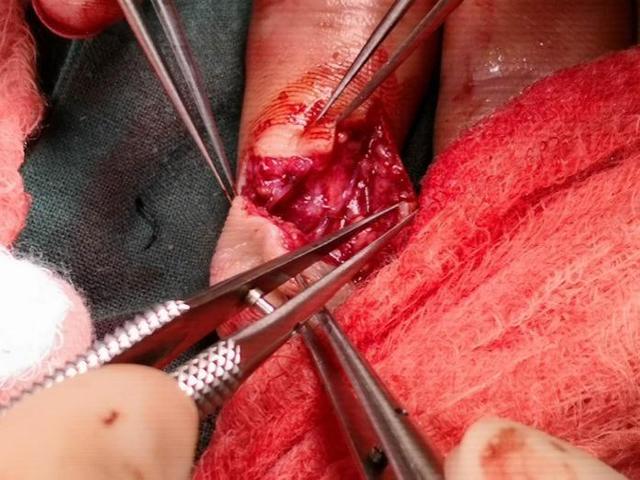

医生先给患者打好了止血带,减少患者的伤口出血。然后开始边清洁伤口,边寻找患者被切断的动脉和神经,找到后先保护起来。因为动脉影响到了手指的供血,如果手术过程中再被损伤,那手术的难度会进一步加大;而神经则影响到手指感觉的恢复,如果破坏严重,就算血管接通,断指能存活,之后也会是麻木而没有正常感觉的。

找到血管和神经之后,确定手术可以顺利的继续进行,便可以先用一根钢针(医生们称之为克氏针)把断掉的骨头重新连接起来固定好,通过X光,我们可以确定骨头的位置和钢针的位置正确,之后,便到了整个手术最重要的阶段——把断掉的血管和神经再接起来。

电线断了、水管漏了我们都可以很容易的换一根,但是血管和神经断了却没法更换,或者说极难替换,但是我们可以用针线像缝衣服一样把血管再接好。但是,接血管的难度完全不是缝衣服可以相比的,因为我们的血管可能还没有缝衣针粗,医生需要在显微镜下,借助特殊的手术器械,用比牛毛更细的针线细致的接好血管。这是技术活,要求非常高,需要医生经过长期的训练才能掌握。如果针缝的少了,血还会顺着断端流出来;如果血管对接的不够好,则容易出现血栓,堵住血管,导致手指坏死。每接好了一根动脉,还需要接上静脉,这样流入断指的血才能流出去,否则血都堵在断指里,也会引起坏死。

血管接好之后,尝试性的放开之前被关闭的动脉,血流通畅,同时吻合口也没有漏口。医生便放心的进行下一步,把神经也接上。当断指重新恢复血色,手术也基本算是成功了。但其实,到这里治疗才进行到一半。